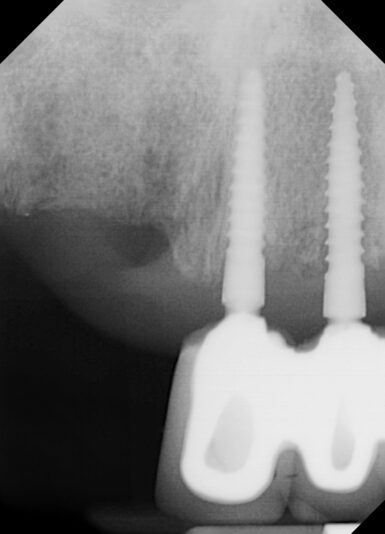

• I know this is an implant study club but I wanted to share a disappointment I had in my most recent bone graft. Patient came in for second opinion and after going over options and non restorable #31 I extracted and grafted the site. Post op PA showed that the M canal and defect was still present. This did have a buccal wall defect and I placed…

Read more